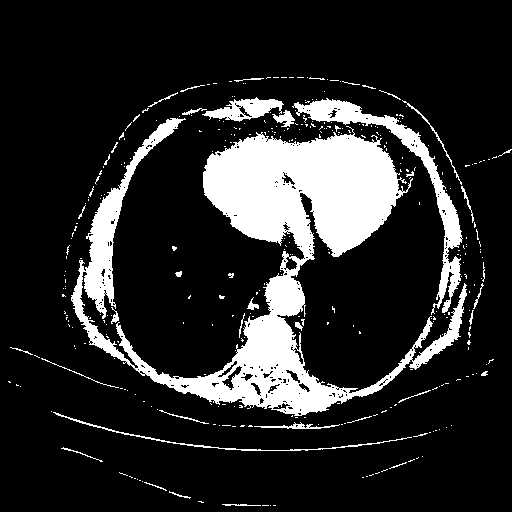

Slice 70 Targeting Evaluation

Patient ID: BC23122020

Model: cytran

Slice: Slice_70

Slice Thickness: 2.5mm

Conversion: NATIVE β VENOUS

4Γ3 grid: Rows show different image types (Original NATIVE, Reconstructed NATIVE, Original VENOUS, Generated VENOUS), Columns show windowing techniques (No Window, Lung Window, Mediastinum Window)